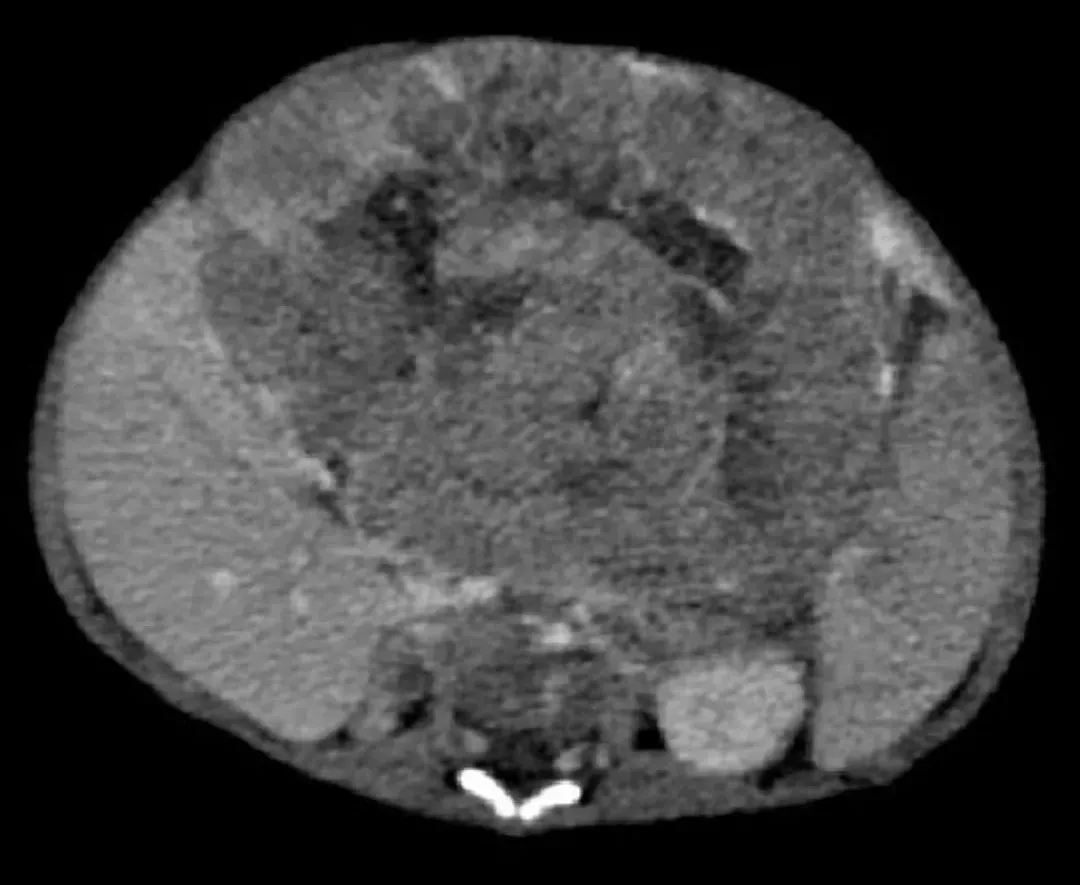

▲2月婴儿巨大肝母细胞瘤

结合手术方案,邓洪强团队为患儿行全麻下肝肿瘤切除术。术中见肿瘤位于肝左叶,大小约12×10cm,占据了绝大部分左肝,肿瘤不仅大,还距离肝脏门静脉很近,增加了手术难度。邓洪强细心分离肝脏重要血管、结扎肿瘤血管,减少术中出血。期间,患儿曾一度出现血压低,心率下降等情况,危及生命,小儿外科医师团队与手术室麻醉医师通力合作,最终顺利将肿瘤完整切除,患儿生命体征平稳。